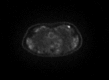

Paraneoplastic polymyositis presenting as a clinically occult breast cancer

Paraneoplastic syndrome affects less than 1% of cancer patients. Diagnosis of paraneoplastic syndrome with neurological presentation requires screening for an underlying malignancy, including a complete history, physical examination and imaging studies. Treatment often results in symptom stability, rather than improvement. Paraneoplastic polymyositis can precede or instantaneously occur at diagnosis or treatment of a primary tumour, while neurological symptoms can persist even following cancer treatment. We report a rare case of metaplastic breast carcinoma with an unusual presentation of paraneoplastic polymyositis.